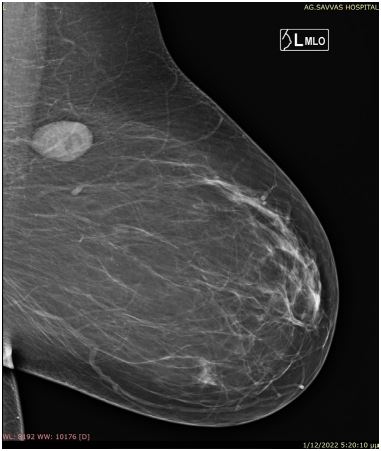

A 45-year-old Caucasian female attended our outpatient clinic during her annual follow-up, with a painless, palpable mass in the upper outer quadrant of her left breast. She denied family history with breast or gynecological malignancies and had never received hormonal therapy or other medication. A clinical examination revealed a painless palpable mobile lump in the aforementioned area at a distance of approximately 10 cm from the nipple. There was no axillary or supraclavicular lymphadenopathy. The other breast was into normal appearance and consistency. The lesion had incidentally been found two years previous to this during her annual mammogram and was originally considered to be fibroadenoma. That ultrasound had detected a hypoechoic oval shape nodule, with no detectable Doppler flow, located in the upper outer quadrant of the left breast, measuring 2.6 cm (Figure 1). The follow-up mammogram detected an enlarged, dense, well-circumscribed oval lesion with no calcifications inside or around, without lymphadenopathy (Figure 2). The lump was classified as category 4 according to BIRADS (Breast ImagingReporting and Data System) criteria. Based on clinical and imaging findings, a Tru Cut biopsy through U/S was then conducted. The resulting pathology revealed spindle cells with elongated cigar-shaped nuclei and eosinophilic cytoplasm (H+E stain x 20) (Figure 3). Despite the benign nature of the tumor, the patient was offered the option of surgical removal of the lump in order to avoid diagnostic dilemmas and pitfalls. A consent form was signed and under general anesthesia the lesion was resected in macroscopic clear margins leaving a drain in place. Postoperative course was without noteworthy incidence and the patient was discharged the hospital the next day. The pathology of the specimen showed intersecting fascicles of elongated smooth muscle cells with no atypia or mitotic activity. Immunohistochemistry depicted strong expression of desmin, a characteristic of smooth muscle neoplasms, which confirmed the diagnosis of leiomyoma, while the absence of p63 marker excluded metaplastic carcinoma (Figures 4,5). Two years after the operation the patient has no symptoms and the mammogram shows no evidence of recurrence.

Figure 2: Round mass in the upper outer quadrant of the left breast without lymph nodes enlargement.